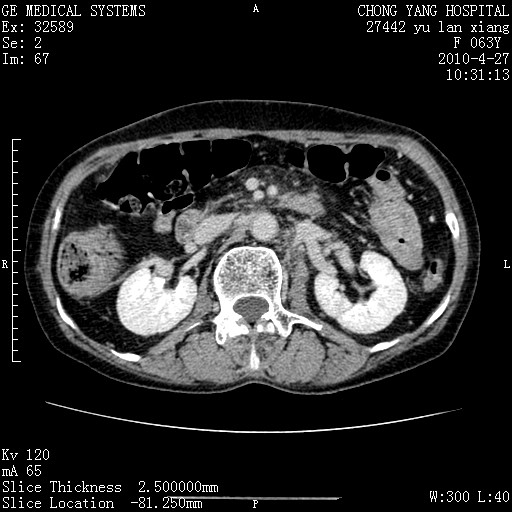

标题: CT26066:F63Y 上腹正中压痛半月,CA199:7400u/ml,MR示胰腺炎伴 [打印本页]

胰腺癌侵犯腹腔动脉干-分支、胃壁、左侧膈肌伴胰周及腹膜后淋巴结转移、胆囊切除术后。

胰腺癌侵犯腹腔动脉干-分支、胃壁、左侧膈肌伴胰周及腹膜后淋巴结转移、胆囊未显影。